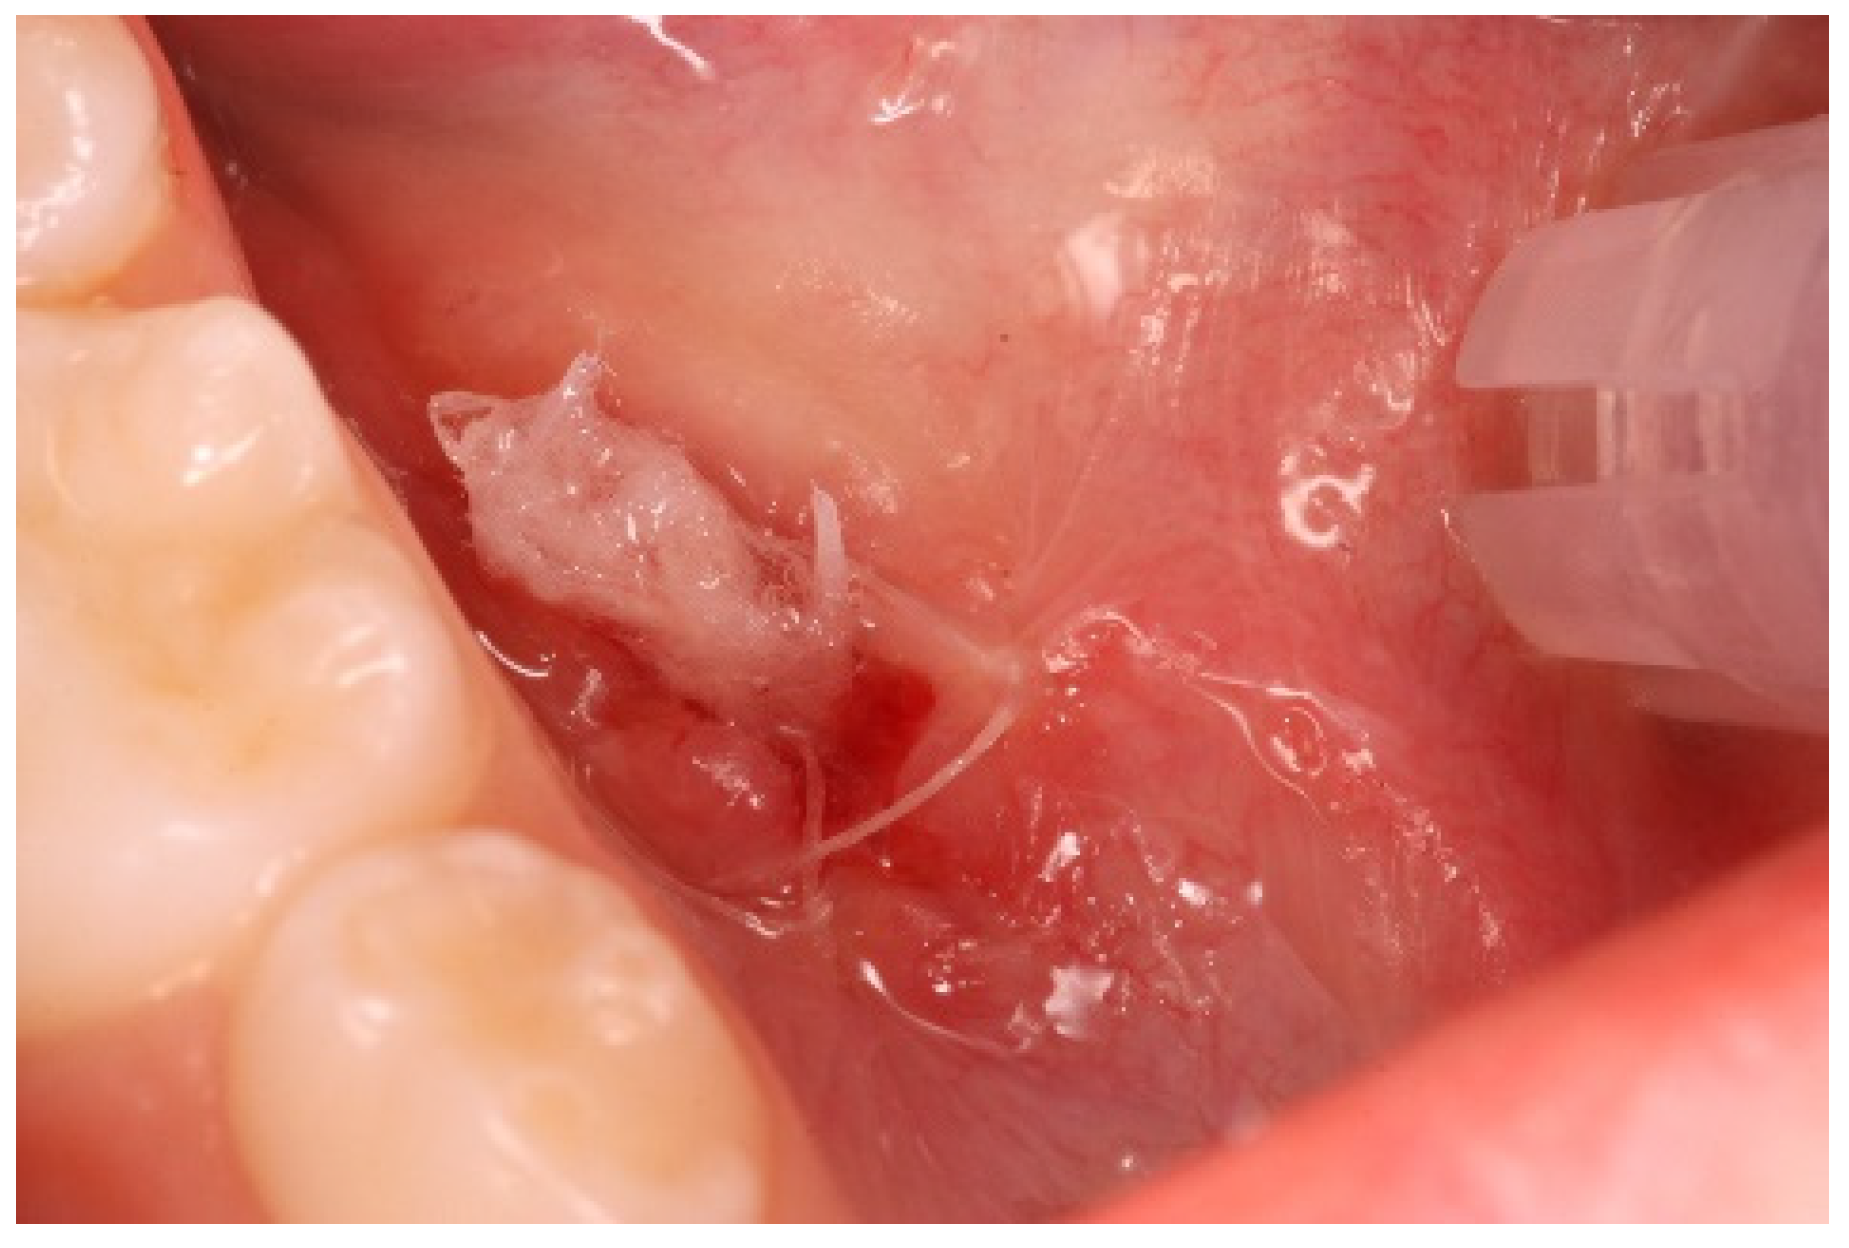

- Incision. Soft tissue incisions with microsurgical scissors to remove the pseudocystic dome and provide adequate access to the area of interest.

- Probing and irrigation. The lumen of the lesion was probed, irrigated with sterile saline solution, and dried with cotton gauze.

- Application of Hybenx®. Hybenx® gel was injected into the lumen of the lesion. The choice of gel was based on its consistency to avoid dispersion of the product into the surrounding tissues. The gel (0.5 mL) was allowed to act for approximately 20 s and then aspirated, and the area was rinsed with copious amounts of saline solution. After complete and careful gel removal, the lesion margins appeared opaque white, with no signs of bleeding.

- Suturing. To delay closure of the ostium and inversion of the margins of the lesion, horizontal mattress sutures (6-0 coated Vicryl® undyed 1 × 18″ s-14 double armed—Ethicon®) were performed to evert the wound edges and keep the ostium open (Figure 5).